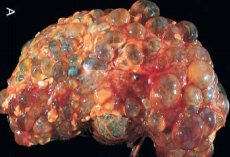

*The mutation is in PKD1 and PKD2 for genes that produce polycystin 1 and 2 proteins. This protein is a signaling protein in the tubules that signals pressure levels. Mutations result in fluid accumulation and development of fluid filled cysts later in life.

*Autosomal Polycystic Kidney Disease. 10-30% of patients get this in the cerebral Circle of Willis.